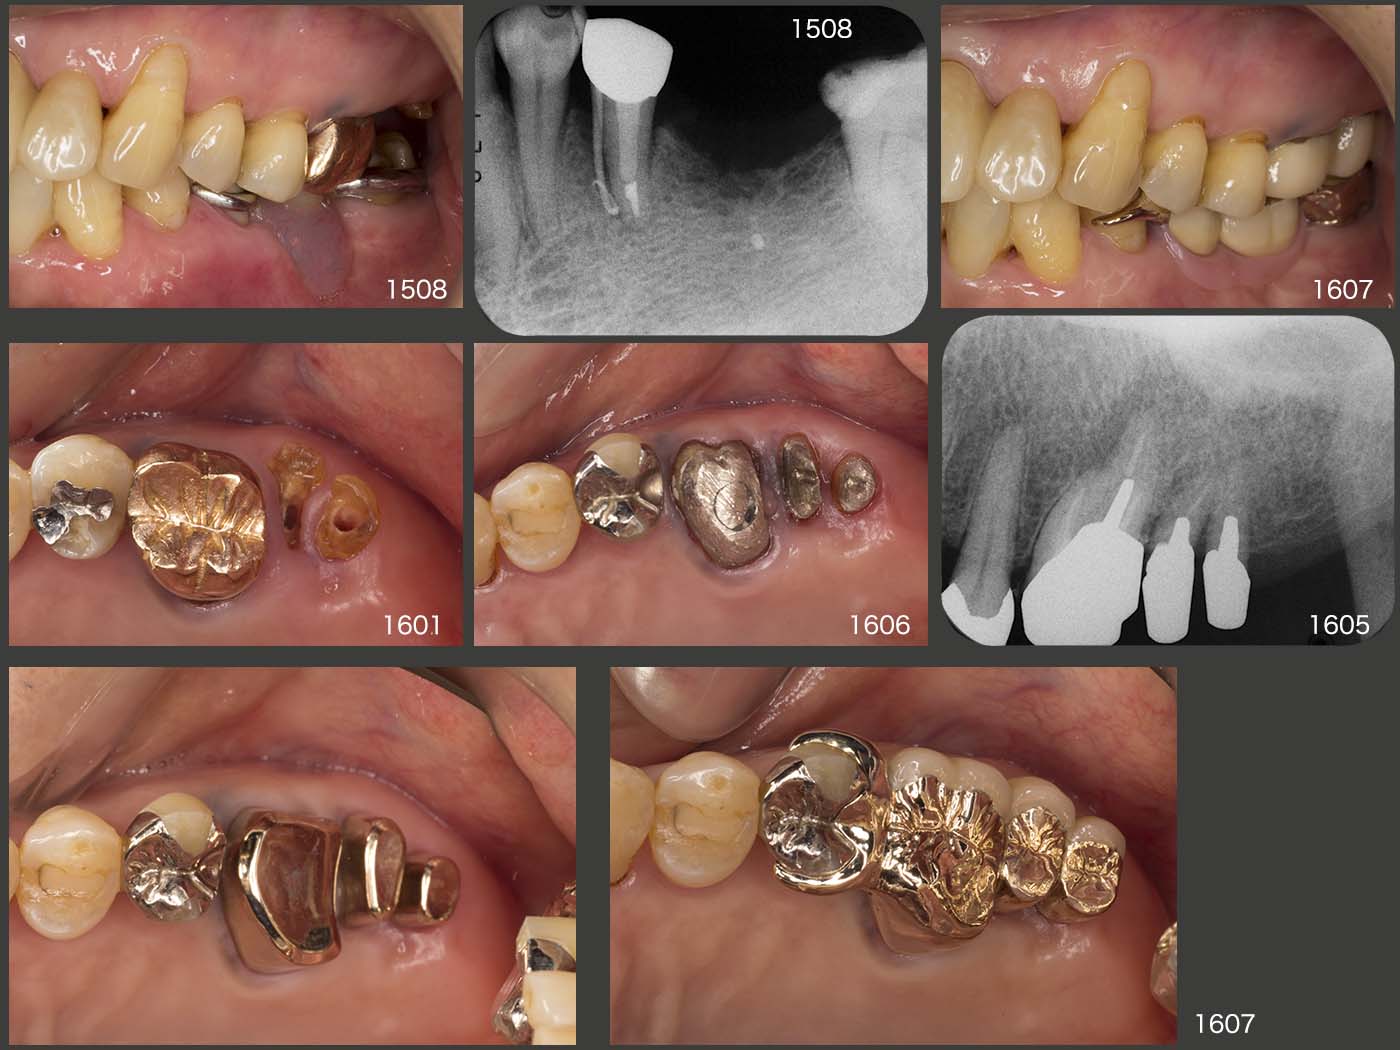

左上7の頰側根は,16年1月に歯冠長延長術を施し,歯肉縁上歯質を確保したうえで保存することにした.単独植立は歯が動揺して無理なため連結固定が必要になるが,清掃性も配慮しコーヌス義歯を選択した.将来,左上7を失うことがあったとしても,同部に義歯床を足すだけですむように,左上5にクラスプを付与した.

2016年7月,初診終了時の状態.右上7(移植歯)の歯周ポケットは最大5mmの値を示した.左上1は初診時より最大9mmの歯周ポケットがみられたが,歯周基本治療以外,特に治療を施していない.その他の残存歯に問題はみられなかった.なお,初診終了時の残存歯の分布から右側が習慣性咀嚼側になることが予想できる.

まず右上7(移植歯)に関しては,2016年12月の時点で歯周ポケットが遠心舌側に7mm認められた.17年5月には10mmになってしまったため,コーヌス内冠を外し,SRPを行うことにした.しかし,術中に歯が脱落してしまった.私の治療の拙さによることは間違いないが,それにしても大きなショックを受けた.一つ言い訳になるが,やはり,この歯が偏咀嚼主機能歯になってしまったことが早期脱落に影響を及ぼしているのではないかと考えている.